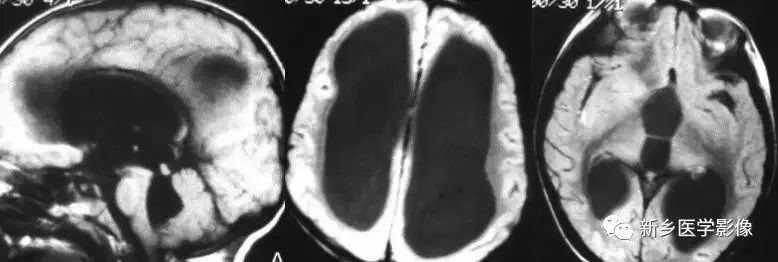

❽ 胼胝体发育不良

胼胝体发育不良可单独发病,但更常见的是伴有中枢伸经系统的其他畸形,包括胼胝体周围脂肪瘤、脑膨出、交通性脑积水、Chaiar-II畸形、Dandy-Walker囊肿、脑裂畸形等。

临床上可无症状或仅有轻度临床症状,临床检查可见眼距过宽、大头畸形、智力发育迟滞等。

胼胝体缺失时,MR冠状位上侧脑室前角呈新月形表现,侧脑室体部分离,呈垂直状平行走行。

04

三脑室及侧脑室同时扩大

❶ 导水管狭窄

中脑导水管是脑室系统最狭窄的通道,也是脑脊液循环受阻最常见的部位。

导水管粘连主要见一于颅内感染和出血后,可于胚胎期发生,也可见于出生后任何年龄。导水管粘连所致狭窄多位于导水管远端。狭窄段长度通常为2一5mm,狭窄近端异水管可呈喇叭口样扩张。

导水管狭窄时,三脑室扩大常很显著,三脑室前部视隐窝和漏斗隐窝扩张或消失,三脑室后部松果体隐窝和松果体上隐窝明显后突,向小脑上池疝入。严重者可压迫小脑。